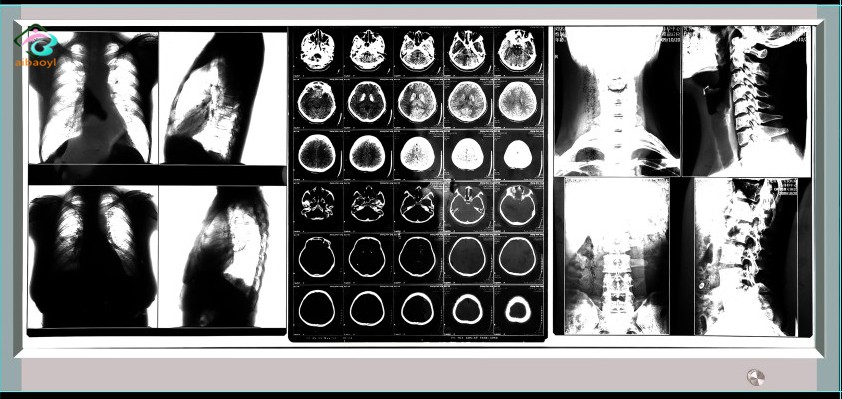

观片灯系列应用 单联、双联、三联、四联

观片灯系列应用

7.1观片灯规格有单联、双联、三联、四联。单联为最小尺寸单位,其余各联观察屏尺寸为单联尺寸的倍数。

产品图片如上